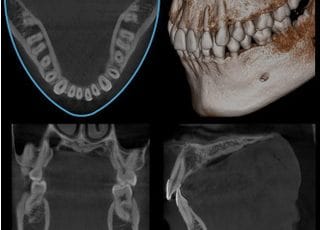

当院では歯科用CT撮影装置を導入しています。

CT撮影装置(Computed Tomography)は、レントゲン撮影データをコンピュータで計算処理し、立体映像や断層写真を得ることができる装置です。歯科用CTは、機種や撮影範囲などにより違いはありますが、一般の医科用CTと比べ、被曝量が非常に少ないのが大きな特徴で、撮影時間も十数秒で済むことから患者さまへの負担を軽減しています。また、歯科用CTでは、歯が失われた部分の骨の厚みや深さ、上顎洞や下顎管までの距離を0.1ミリ単位で計測し、歯牙や上顎洞の形態の三次元的イメージを把握できます。

【見えなかったものが見える】

一般のレントゲンで見えなかった部分が容易に確認できるようになりました。顎骨の形や内部構造なども、様々な角度から検証することができます。

【わからなかったことがわかる】

上顎洞(上顎骨の中央にある空洞)の形態や粘膜の状態、病巣などを立体画像で確認できます。

【治療の可能性が広がる】

診断や治療において2次元でのレントゲン写真の情報のみでは、歯科医師の経験や指の感覚に頼る部分も意外に大きいものがありました。

CTから得られる詳細な情報があれば診査・診断がより精密になり、治療の可能性を広めることができます。

【インプラント治療での活躍】

CT撮影により大きな血管や神経を傷つけずにインプラントを骨の中に植えることが可能か、術前診査できるのでインプラント治療がより精密なものになります。